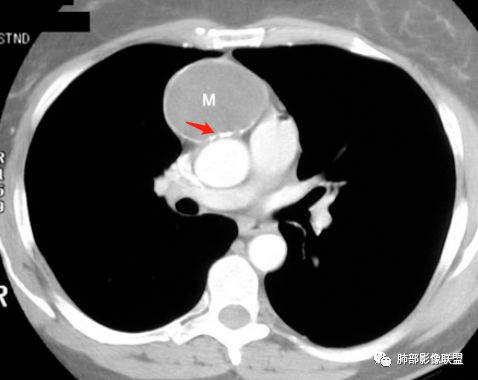

右侧前纵膈肿块,边缘分叶,病灶中心可见斑块状钙化,实性成分明显持续强化,考虑胸腺瘤。

胸腺瘤

王兆宇老师:畸胎瘤总有油脂物质密度,块状钙化少见,环状钙化多见,头结节骨化多见,畸胎瘤钙化不在中间。

胸腺瘤钙化

大部分钙化还是包膜钙化和条状,结节状钙化,团块状钙化也比较少。位置中央,周围都可以。